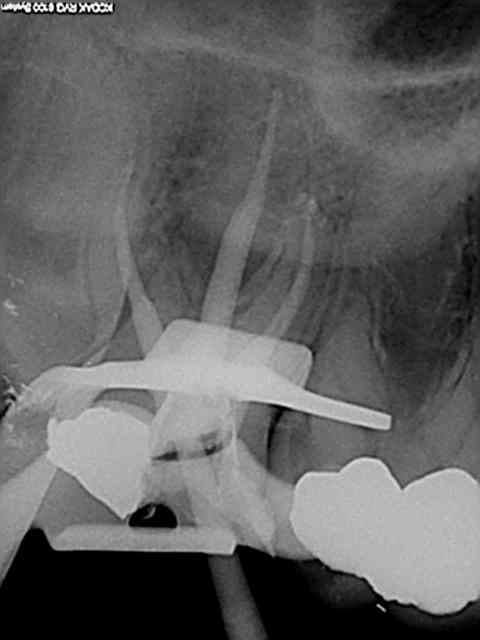

Et une de plus !

R19 vxiysf - Eugenol

R20 kboz6l - Eugenol

01 ukhwbq - Eugenol

C'est pas de la frime hein, mais ca fait plaisir d'avoir trouvé ENFIN une technique rapide et reproductible sans casse. (enfin presque il y a dans le tas un micro morceau de R25 pas loin de l'apex )

Bravo ! Belles images